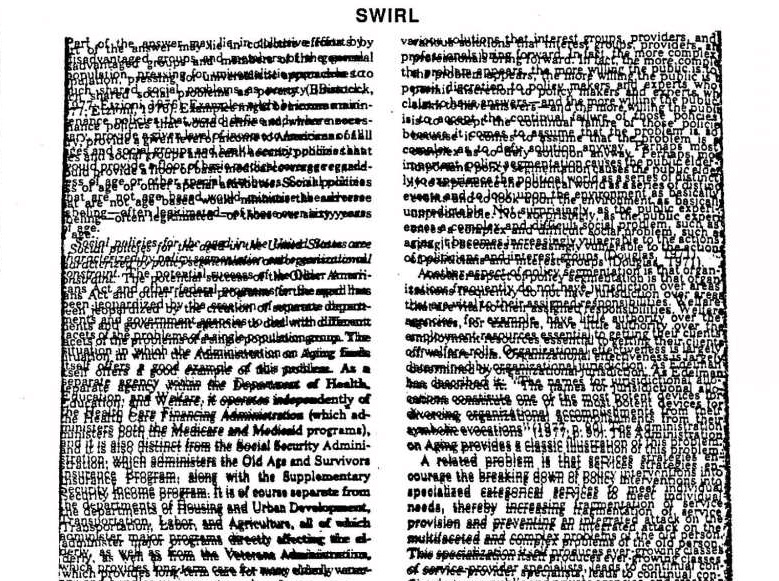

Swirled print distortion suffered by some people with visual perception processing problems

Since 1980, research has repeatedly documented the presence of, and difficulties associated with, a little known perceptual processing problem known as Irlen Syndrome. Irlen Syndrome is a problem with how the brain interprets visual information. The condition affects 12-14% of the general population and up to 46% of individuals with reading and learning difficulties. It is characterised by a variety of physical symptoms exacerbated by environmental factors such as lighting, especially bright lights and fluorescents, and computer screens, iPhones, white paper, white boards, high contrast and visually-intensive activities. Unfortunately, eye care professionals are unfamiliar with the warning signs of Irlen Syndrome. As a result, many individuals with this condition go unidentified and never receive proper intervention for their visual-perceptual processing problems.

Individuals with Irlen syndrome will often complain of light sensitivity associated with sunlight, bright lighting, fluorescent lights, headlight and glare. They may also have reading problems, as reading becomes inefficient and they may need to re-read for comprehension or build breaks into reading. High contrast (black print on white paper) and visually-intensive activities, create high levels of stress for the brain that trigger physical symptoms which may include headaches and migraines. Brain imaging, both SPECT scans and fMRI, of individuals with this condition shows over-activity, complex brain patterns and non-normalised functioning. This results in a variety of issues, including difficulties reading because of a lack of print stability, issues with glare or discomfort from the white background on the printed page, problems with depth perception and physical symptoms, such as headaches, nausea, dizziness, brain fog, anxiety, strain and fatigue.